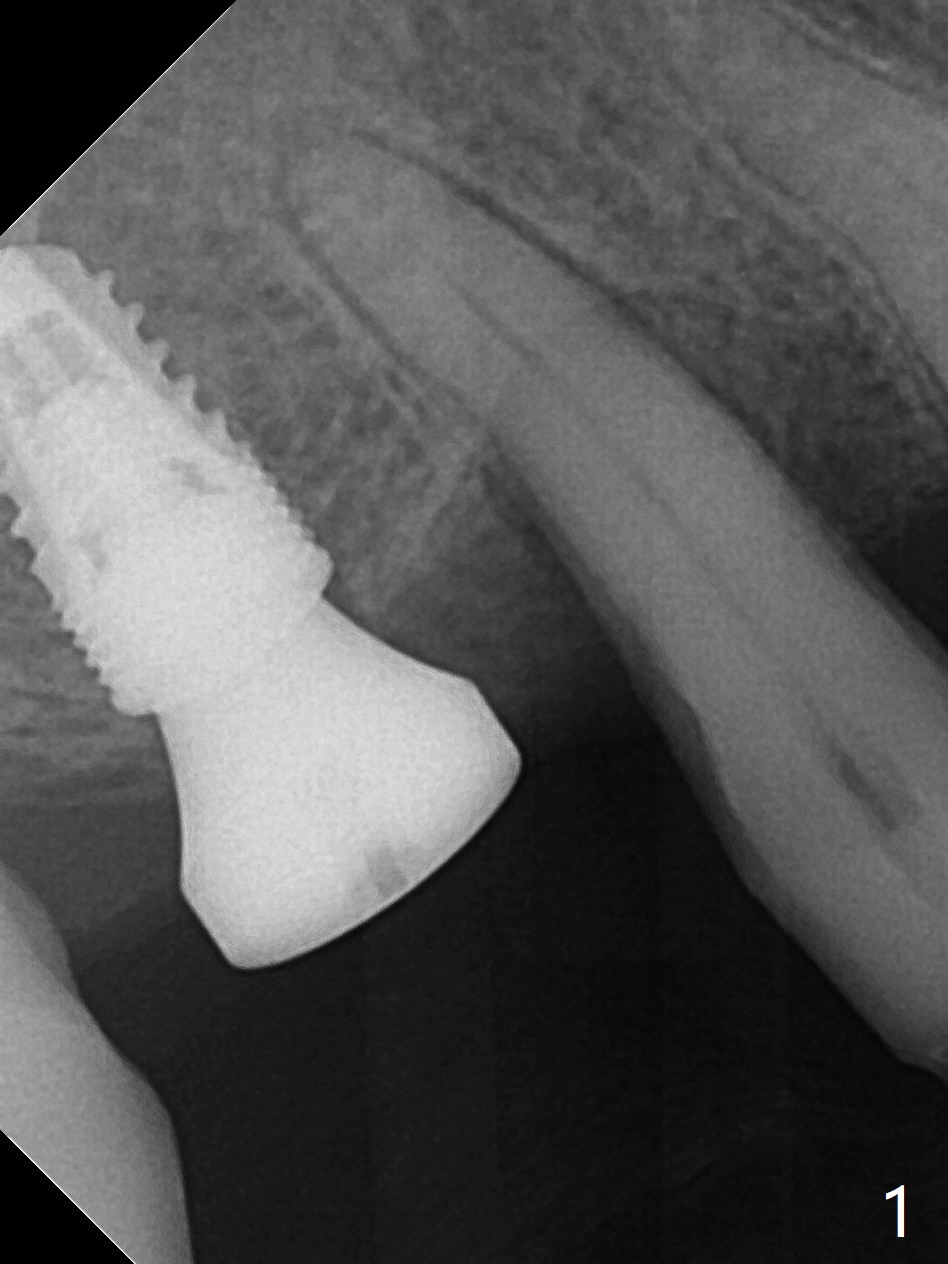

After osteotomy at #3 with IS guide, a 4.5x8 mm SM implant has to be placed free hand because of mismatch of the SM implant and IS guided fixture driver. With minor adjustment, the implant is placed subcrestal to reduce chance of future periimplantitis (Fig.1,2). There is oozing in the osteotomy, which seems to stop when the implant and healing abutment are placed. The patient returns with oozing next day. The temporary FPD is removed. The oozing is coming from the area around the healing abutment. Gauze pressure appears to be effective. After application of periodontal dressing (Fig.3 D) around the healing abutment, the temporary FPD is inserted (T). Hemostasis occurs. Fig.3 is taken 7 days postop. The implant remains subcrestal 3 month postop (Fig.4). A 5.8x7(3) mm cemented abutment is placed for a separate provisional.